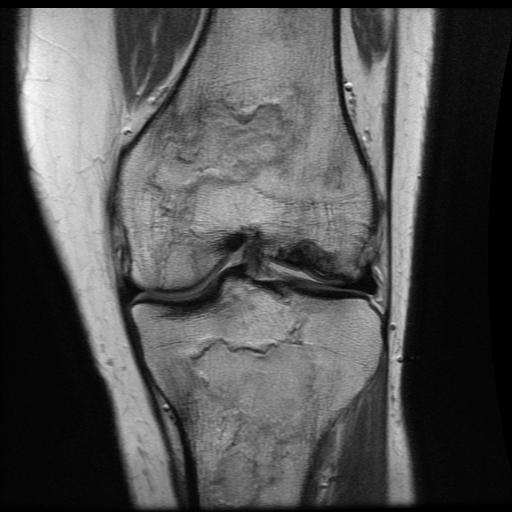

MRI

More extensive involvement through knee